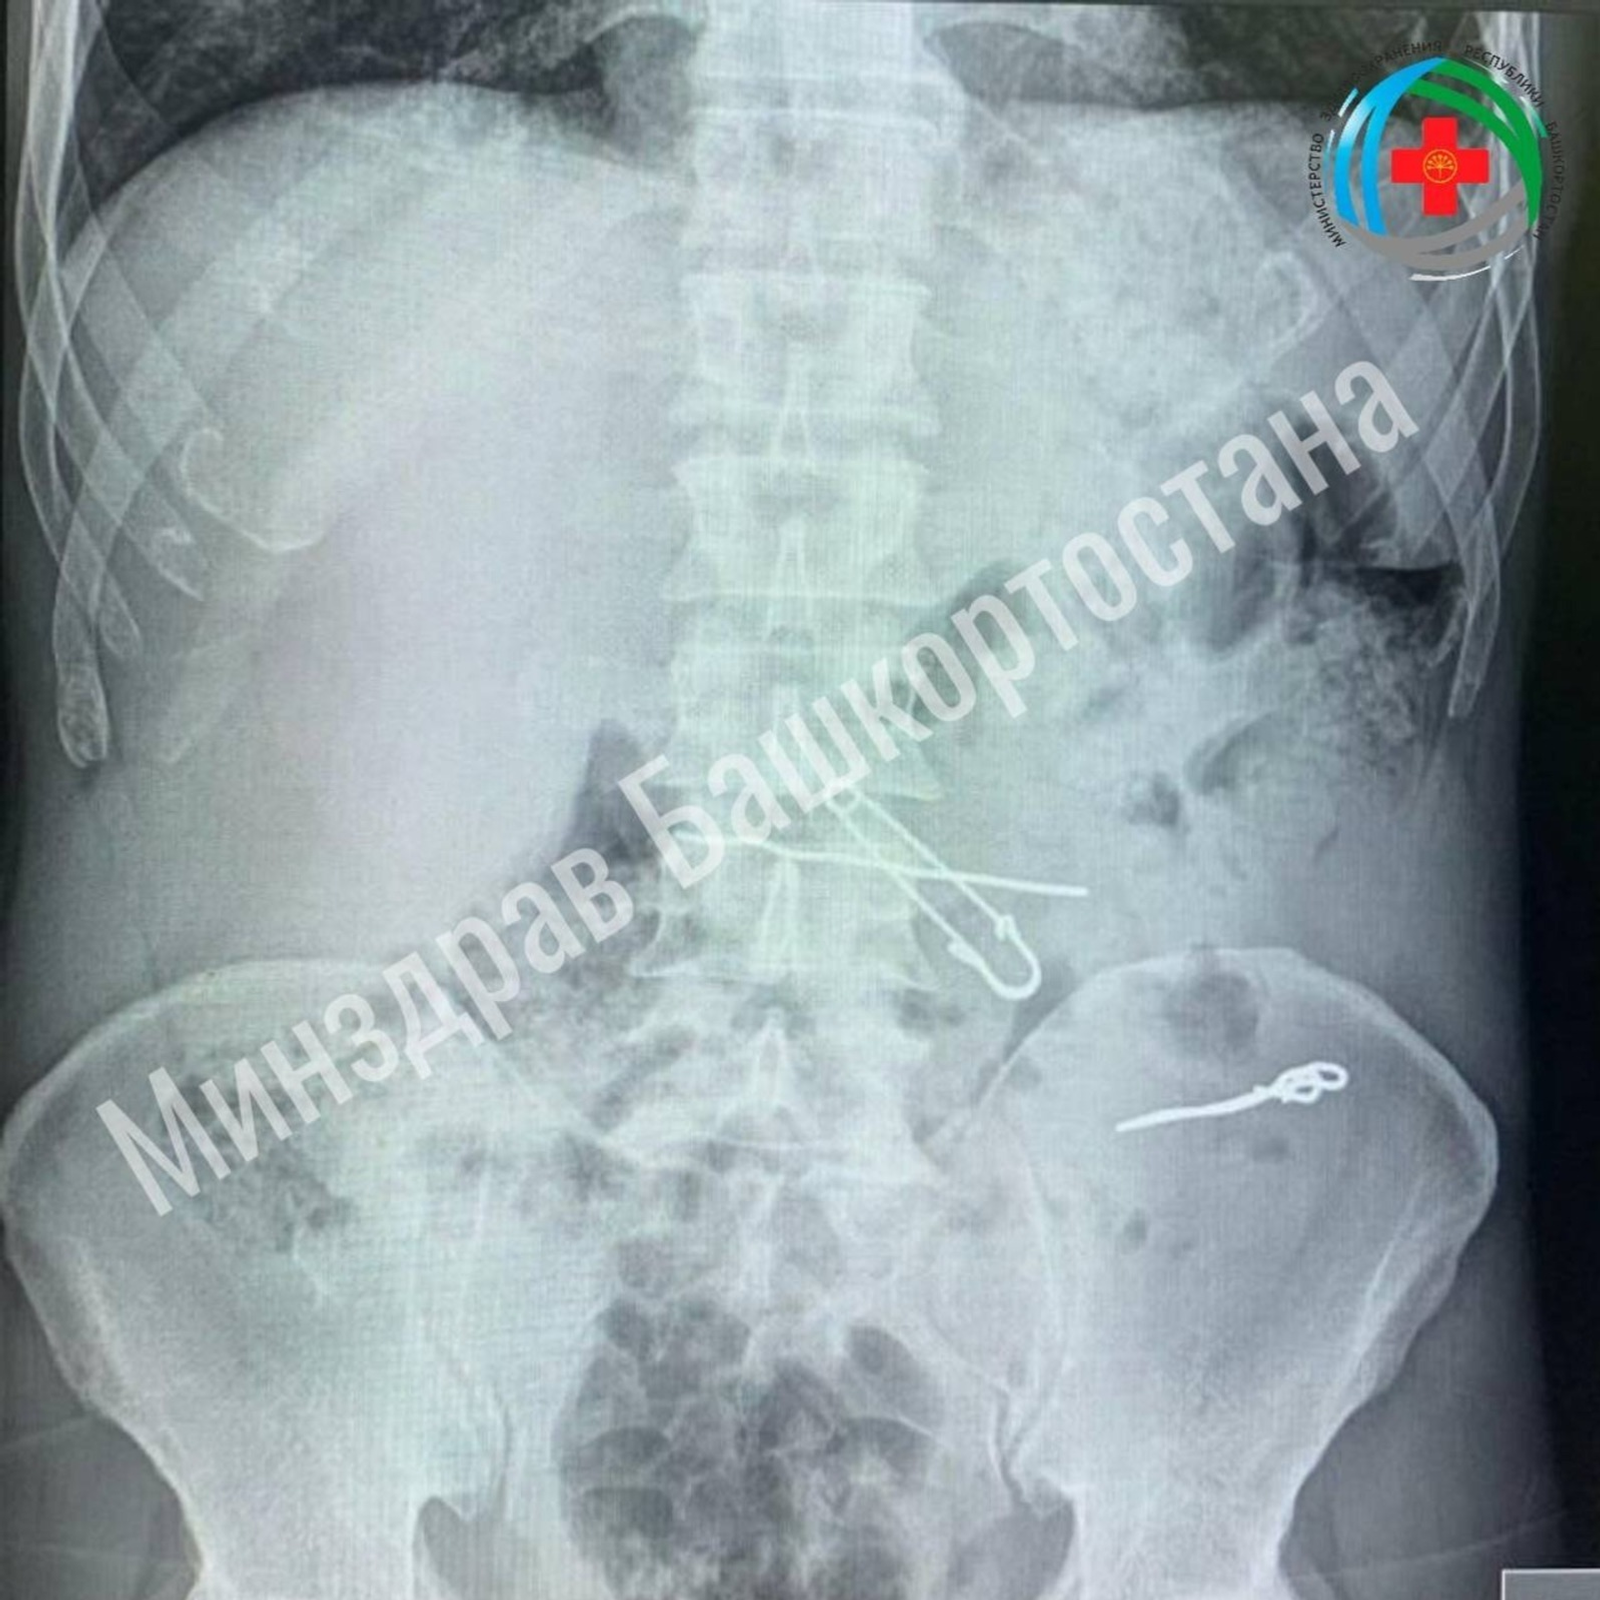

Об этом случае рассказал министр здравоохранения Башкирии Айрат Рахматуллин. Пациенту срочно назначили рентген-исследование. В результате в его толстой кишке высветились проволоки, несколько скрепок различной длины: 47, 62 и 90 мм. В желудке обнаружилось присутствие еще двух инородных предметов: булавки и проволоки. Мужчину поместили в стационар и прооперировали.